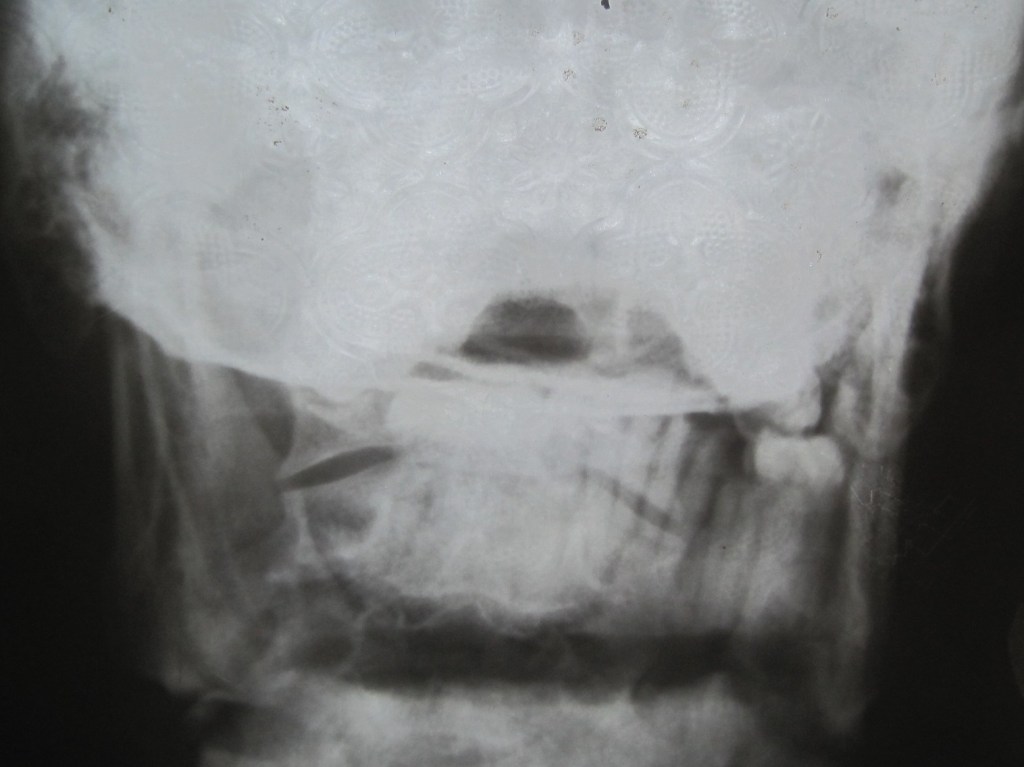

A compound fractured mandible from a machete injury.